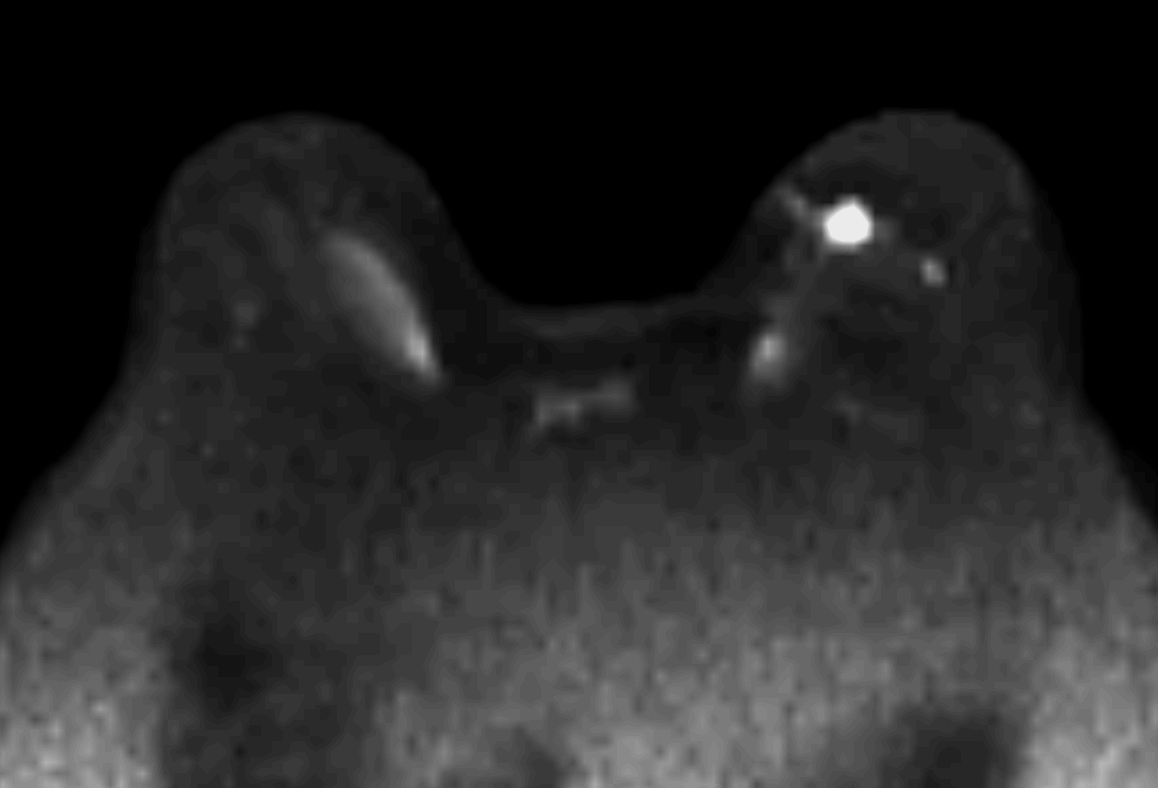

Axial DWI (b1500)

-